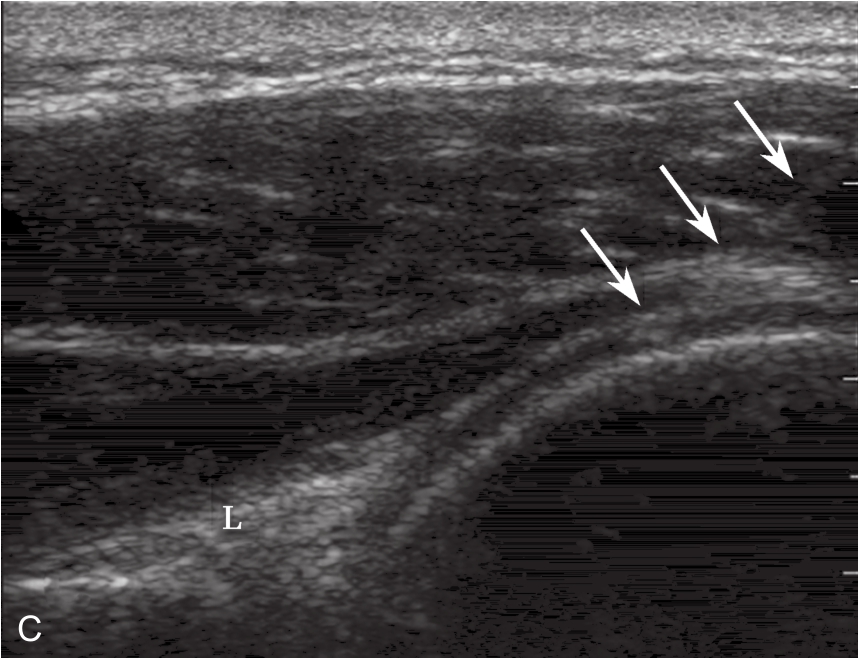

▲ 图2-6-5 超声引导下肩关节腔介入治疗超声图(三)

A.患侧肩关节下关节囊增厚;B.对侧正常关节囊;C、D.注射治疗后扩张的关节腔内粘连带;双星号:关节囊;箭头:粘连带;单星号:关节腔